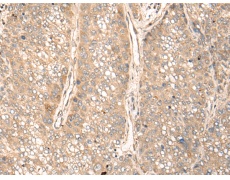

IHC positive control: |

Human liver cancer |

IHC Recommend dilution: |

25-100 |